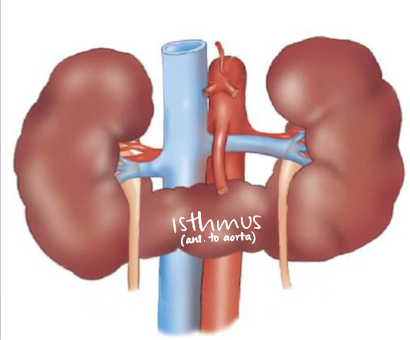

horseshoe kidney

fusion of lower poles, connected via isthmus (anterior to spine and AO)

??